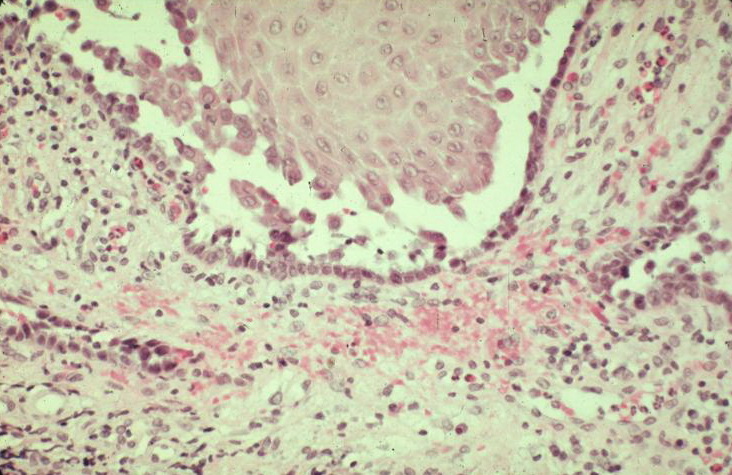

The earliest recognized change may be either eosinophilic spongiosis rarely or, more commonly, “spongiosis” in the lower epidermis . This spongiosis may actually represent the earliest manifestation of acantholysis rather than true spongiosis as defined earlier. Acantholysis leads first to the formation of clefts and then to blisters in a predominantly suprabasallocation . The intraepithelial acantholysis may extend into adnexal structures or occasionally be higher in the stratum spinosum. The basal keratinocytes, although separated from one another through the loss of attachment, remain firmly attached to the dermis like a “row of tombstones.” Within the blister cavity, the acantholytic keratinocytes, singularly or in clusters, have rounded condensed cytoplasm about an enlarged nucleus with peripherally palisaded chromatin and enlarged nucleoli. In some patients, there are varying quantities of antidesmoglein 1 and antidesmoglein 3 antibodies, leading to variable planes of acantholysis. There is little inflammation in the early phase of blister formation. If present, it is usually a sparse, lymphocytic perivascular infiltrate accompanied by dermal edema. However, if eosinophilic spongiosis is apparent, numerous eosinophils may infiltrate the dermis. The phenomenon of eosinophilic spongiosis occurs occasionally in other blistering diseases, particularly in their early phases, including acute contact dermatitis, pemphigus foliaceus, bullous pemphigoid, herpes gestation is, drug eruptions, spongiotic arthropod bite reactions, and transient acantholytic dermatosis. Several important changes ensue as the lesions age. First, a mixed inflammatory cell reaction consisting of neutrophils, lymphocytes, macrophages, and eosinophils may develop. Because of the instability of the blister roof, erosion and ulceration may occur. Older blisters may also have several layers of keratinocytes at the blister base because of keratinocyte migration and proliferation. Last, there may be considerable downward growth of epidermal strands, giving rise to so-called villi (Fig. 9-9D). The evaluation of patients with only oral lesions is difficult, because intact blisters are rarely encountered due to the trauma of mastication, and biopsies may show only erosion and ulceration. Indeed, it is best to sample the edge of a denuded area with intact mucosa in an attempt to demonstrate the typical pathologic changes. Clinicians frequently cannot distinguish between an ulcer and the intact mucosa, as both are often white and shaggy. In patients with only oral lesions, biopsies of intact oral mucosa for DIF testing are more sensitive than biopsies of lesions for routine light microscopic evaluation. Therefore, biopsy from the normal maxillary and upper buccal mucosa is necessary when there is extensive ulceration. Cytologic examination using a Tzanck preparation is useful for the rapid demonstration of acantholytic epidermal keratinocytes in the blisters of pemphigus vulgaris. For this